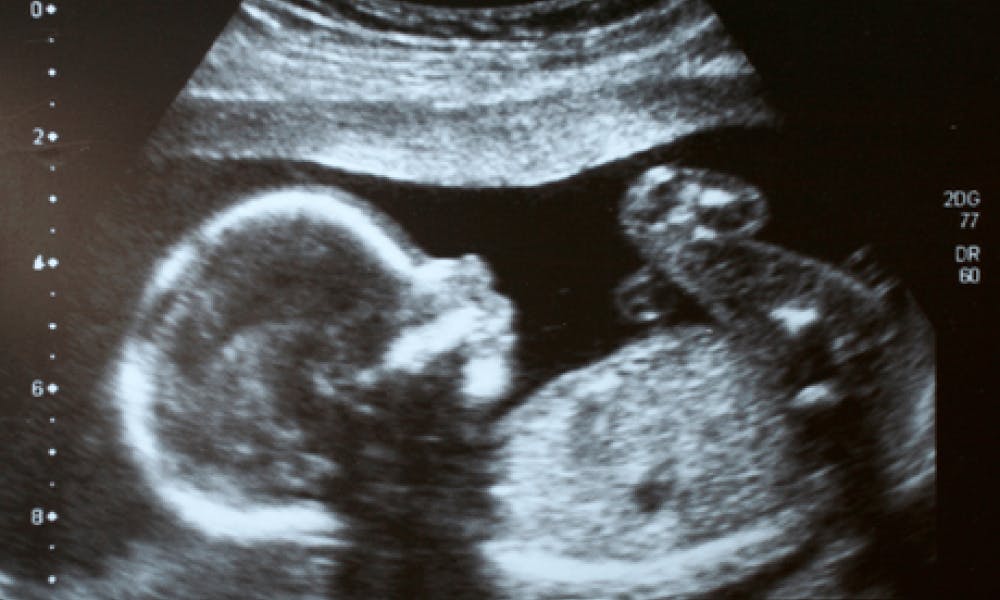

For over 60 years, Wellbeing of Women has been transforming the UK landscape of women’s health. Their funded research has led to landmark discoveries — including linking HPV to cervical cancer, pioneering the use of ultrasound in pregnancy, and developing new treatments for endometriosis.

Wellbeing of Women’s research established ultrasound as a standard part of prenatal care used all over the world — helping detect birth defects early and saving mothers and babies.